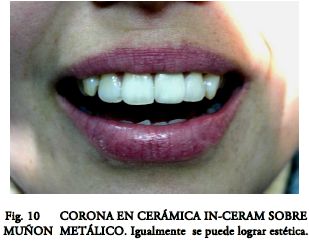

Actualmente existe una abrumadora presencia de trabajos que avalan su uso (7, 8, 12, 13, 14). Sin embargo en nuestro país no han desplazado de forma automática a las técnicas tradicionales. Quizás porque nuestra escuela restauradora clásica (15), basada en aleaciones coladas nobles (y conservadora al máximo de los tejidos dentarios) (Fig.7 a 10), ha obtenido un éxito predecible a lo largo de los años. Pero sus altos costos, compleja manipulación, su casi imposibilidad de remoción para retratamiento, sumado a la aparición de fracturas graves cuando falla la técnica, abren paso a nuevas alternativas que se están adoptando con la debida prudencia.

Hasta la aparición de los Postes Cerámicos, fabricados en base a Óx. de Circonio (ZrO), la posibilidad de lograr efectos ópticos similares a los dentarios era impensable. Los sistemas cerámicos no se han impuesto (entre otras causas) por presentar espesores poco conservadores y ser muy rígidos y estresantes con el riesgo de provocar fracturas radiculares intratables. Sin embargo los nuevos PPF conjugan excelentes propiedades estéticas con muy buenas propiedades mecánicas. Pueden ser “blanco opacos” para disminuir la sombra gris hacia la encía, o “blanco translúcidos” (Figs. 1, 2, 3, 5), para mantener la estética y permitir el pasaje de la luz de curado. Al eliminar la masa interna oscura de los postes metálicos se mejoran mucho las cualidades ópticas. Si bien en coronas metal-cerámica el efecto es inapreciable, es excelente en las cerámicas sin núcleo y para algunos autores también en algunas cerámicas de núcleo (In-Ceram).

- Fabricación del Muñón Coronario.- Esta etapa tan fácilmente resuelta por los colados, siempre es problemática en los prefabricados. En casos de discrepancia entre los ejes coronario y radicular (Fig.7) puede ser necesario cambiar de sistema (Figs. 8, 9, 10).